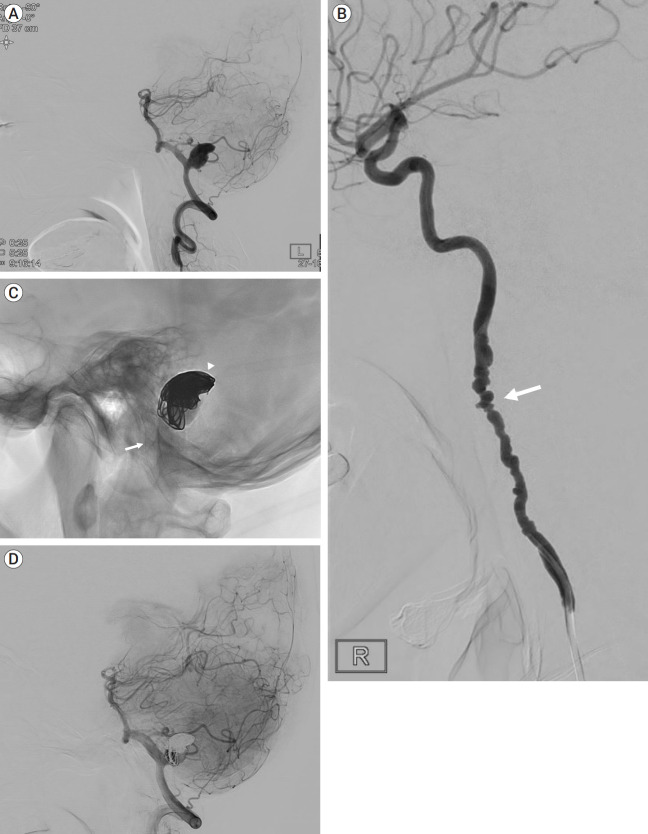

纤维肌发育不良(FMD)是一种主要影响女性的非炎症性动脉疾病。多项研究表明,在经历颈动脉或椎动脉夹层(VAD)的患者中,FMD的患病率增加。本病例报告介绍了一名57岁的女性,她表现出头痛,并被诊断为部分血栓形成的椎动脉巨大动脉瘤。该动脉瘤用分流器和线圈成功治疗,但两周后发现新发的椎动脉破裂,导致内陷。本病例报告强调了对疑似FMD患者的夹层和动脉瘤治疗的认识和理解的必要性。

Fibromuscular dysplasia (FMD) is a noninflammatory arterial diseases that affects predominantly women. Multiple studies have demonstrated an increased prevalence of FMD in patients who experience carotid or vertebral artery dissection (VAD). This case report presents a 57-year-old female who presented with a headache and was diagnosed with partially thrombosed giant aneurysm of vertebral artery. This aneurysm was successfully treated with flow-diverter and coil, but new onset rupture of vertebral artery was detected two weeks later, leading to internal trapping. This case report underscores the need for awareness and understanding of treatment of dissection and aneurysm in patient who is suspected FMD.